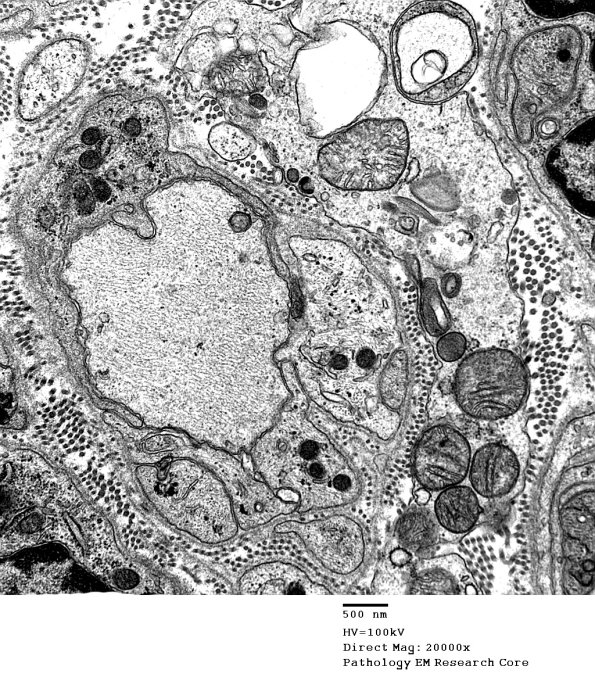

4B3-5 Additional demyelinated axons, some of which show redundant myelin loops. (electron micrographs)